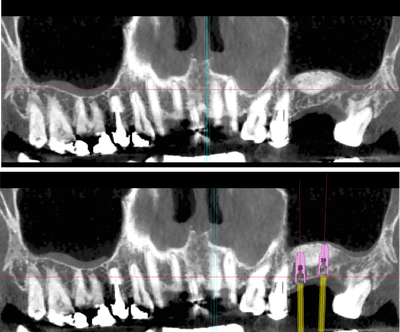

reconstruction osseuse préimplantaire

sinuslift

augmentation osseuse en hauteur

greffe d'apposition

augmentation osseuse en largeur